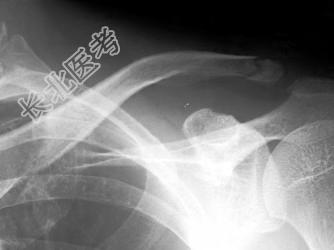

- 单项选择题男,25岁, 外伤后摄片,请结合影像图像选择最可能的诊断 ( )

A、肋骨骨折

B、锁骨骨折

C、原发性气胸

D、肋骨骨折伴气胸

E、锁骨骨折伴气胸